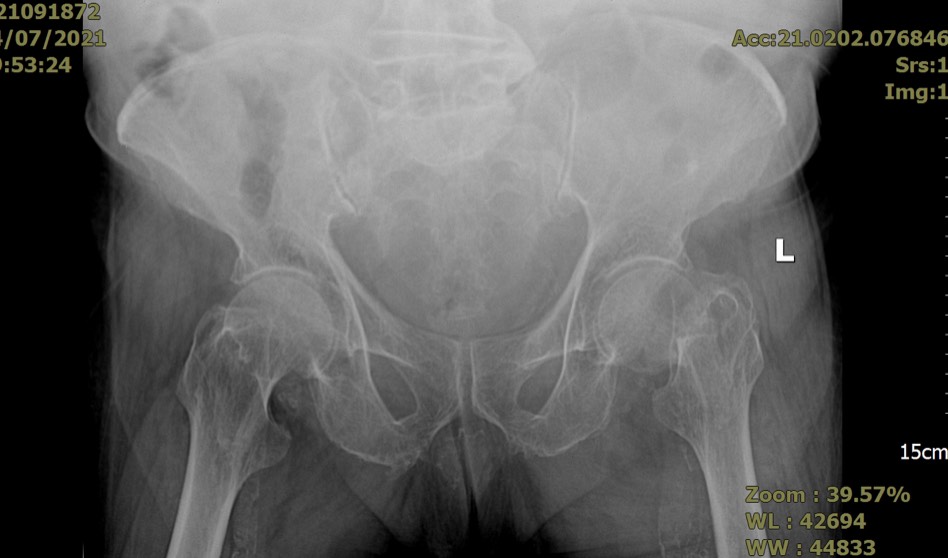

- Hình ảnh trước mổ: gãy cổ xương đùi trái của bệnh nhân